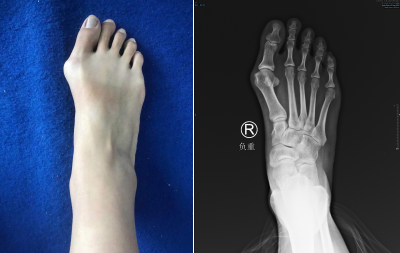

拇外翻长什么样

大脚趾向内倾斜角度逐渐变大,慢慢的大脚趾内测会出现一个肿包,有时会在肿块上产生肿胀。有时候会磨得脚内侧红肿、疼痛,前脚变宽,逐渐找不到合脚的鞋子穿着。

徐明亮主任了解了李女士的情况后,通过检查发现右足踇趾外翻增大,跖骨间受到挤压,所以走路时会产生疼痛。现在医院进行的第四代微创拇外翻矫正手术,除了微创外,进行三维畸形矫正,更好保护组织,更有利于术后早期恢复。

术前

术后